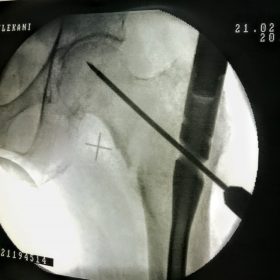

Υποκεφαλικό : Είναι ενδαρθρικό κάταγμα στον αυχένα του μηριαίου (το εσωτερικό του αρθρικού θυλάκου), το οποίο διακόπτει την αιμάτωση της κεφαλής του μηριαίου και οδηγεί σε μη πόρωση του κατάγματος (ΟΣΤΕΟΝΕΚΡΩΣΗ της Μηριαίας κεφαλής). Σε ασθενείς κάτω των 65 ετών αντιμετωπίζεται χειρουργικά με κοχλίωση στις πρώτες 12 ώρες. Τρείς βίδες σε σχήμα Τ με την βοήθεια τηλεόρασης διαδερμικά χωρίς διάνοιξη. Σε ασθενείς από 65-75 ετών γίνεται ολική αρθροπλαστική και σε ασθενείς άνω των 75 ετών αλλάζεται μόνο η κεφαλή χωρίς την αλλαγή της κοτύλης. Ο ασθενής περπατάει άμεσα μετεγχειρητικά στις 5 ώρες και εξέρχεται από το νοσοκομείο σε 1 -2 ημέρες. Στην κοχλίωση μπορεί να εξέλθει και την ίδια ημέρα.